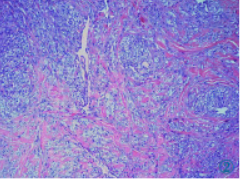

皮肤(右足外侧)病理活检:真皮层见梭形瘤细胞纵横交错排列,梭形细胞被含有红细胞的裂隙样腔隙分隔,呈筛孔状或蜂窝状,在梭形细胞质内或细胞外可见嗜伊红色透明小体,梭形细胞轻-中度异型,可见少量核分裂象,未见肿瘤性坏死。免疫组化:HHV8(个别细胞+),CD34(+),CD31(+),Fli-1(+),Ki-67(阳性率10%)。诊断:卡波西肉瘤(Kaposi’s sarcoma,KS)(图2)。

图2病理(HE)诊断为KS。